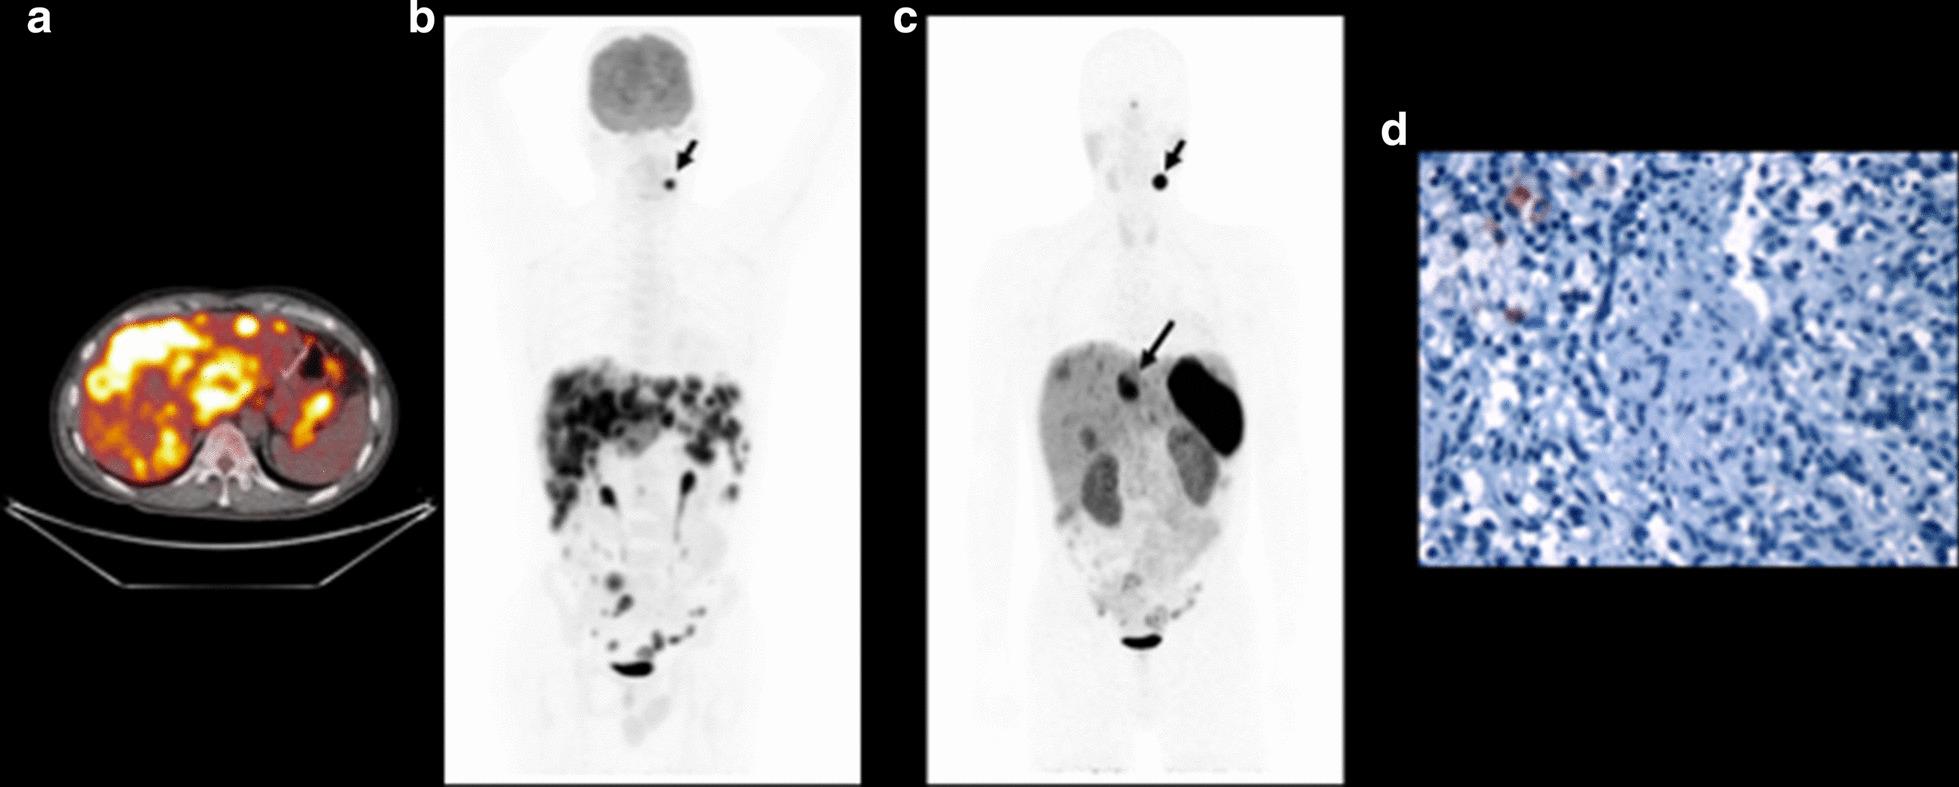

[ Ga]Ga-DOTATATE PET/CT imaging was negative, demonstrating that liver metastases had lower uptake than background liver for nine cases (9/12 cases, 75%) and heterogeneous uptake of somatostatin tracer was noted for two cases (16.6%) of wtGIST. However, [ Ga]Ga-DOTATATE PET/CT demonstrated intense tracer uptake in a synchronous paraganglioma in one case and a metachronous paraganglioma in another case with wtGIST.

[镓]镓 - DOTATATE PET/CT成像为阴性,9例(9/12例,75%)显示肝转移灶摄取低于肝脏背景,2例(16.6%)wtGIST出现生长抑素示踪剂摄取不均匀。然而,[镓]镓 - DOTATATE PET/CT在1例wtGIST患者的同步副神经节瘤和另1例异时性副神经节瘤中显示出强烈的示踪剂摄取。